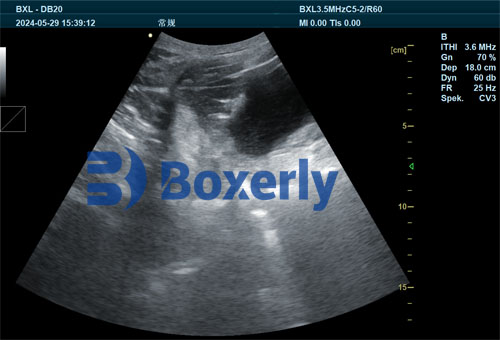

Veterinary ultrasound, particularly B-mode or real-time ultrasound, allows for the visualization of internal soft tissues, including the uterus and mammary glands. On our farm, and in many others across the globe, we begin using ultrasound on sows around 5–7 days before their expected farrowing date. The goal is to monitor mammary development and detect early signs of mastitis or irregular gland formation.

The first 21 days after farrowing are crucial. In our herd management system, we continue to perform ultrasound checks on sows 2–3 times during this period. Postpartum uterine health is a major concern, as lingering infections or poor uterine involution can suppress milk production. By using ultrasound, we assess uterine size, the presence of retained fetal membranes, or fluid buildup, all of which could indicate a developing infection.

Veterinary ultrasound can be used to assess the piglet's digestive system, especially in cases where there is poor feed intake or suspected gastrointestinal issues. By scanning the stomach and small intestine, we can evaluate whether digestion is progressing normally or if inflammation, bloating, or blockages are present.

Studies from the Netherlands and Germany have shown that introducing creep feed not only prepares the piglet’s digestive tract for solid food but also stimulates the development of digestive glands and enzyme secretion. Ultrasound allows us to assess the functional development of organs like the pancreas and liver, ensuring the piglets are physiologically ready for the weaning transition.

We start by offering small quantities of feed multiple times per day—typically 4 to 6 times—to encourage frequent intake without overloading the immature digestive tract. Feed remnants are removed before the next feeding to maintain hygiene and prevent spoilage. Monitoring digestive tract structure through ultrasound confirms the effectiveness of this practice.

To incorporate ultrasound effectively, we train our farm staff to use hand-held ultrasound scanners designed for livestock. These devices are user-friendly and provide real-time imaging of reproductive organs, mammary glands, and digestive systems. Once a health concern is spotted, the veterinary team confirms the diagnosis and prescribes the appropriate treatment or nutritional plan.